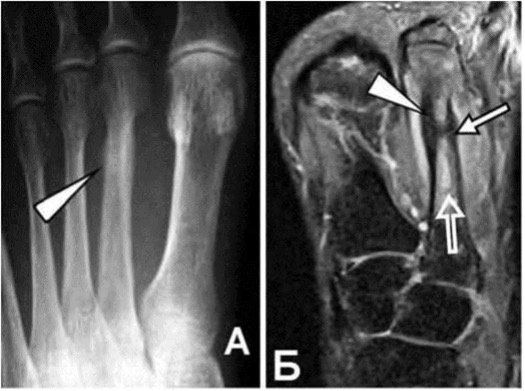

Стрессовый перелом на рентгенограмме (А) и МРТ (Б).

Стрессовые переломы - это вид повреждения кости, когда причина не в одномоментной травме, а в повторяющихся нагрузках.

На ранних стадиях рентгеновское сканирование может не выявить перелом.

Основное лечение - полное ограничении нагрузки (совсем на наступать на ногу) в течение нескольких недель (обычно около 6).

При игнорировании, отек костного мозга может распространиться дальше.

- У пациентки случился перелом пяточной кости, но сохранялся двигательный режим “через боль”, отек с пяточной кости распространился на ладьевидную кость и может пойти дальше на клиновидные кости или привести к полноценному перелому.